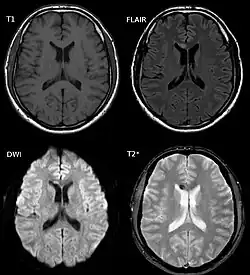

| Two MRI images of a patient with diffuse axonal injury resulting from trauma, at 1.5 tesla field strength. Left: conventional gradient recalled echo (GRE). Right: Susceptibility weighted image (SWI). | |